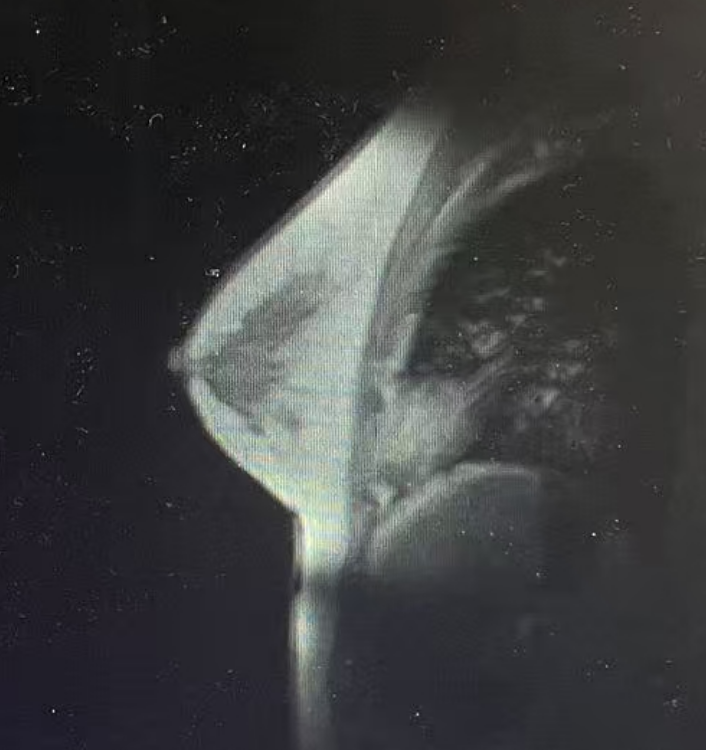

·乳腺彩超

1、右乳9点见一个低回声区,大小约0.53*0.63cm,呈直立生长,边缘成角、毛刺,内部回声不均匀,肿块内未见强回声,BIRADS 5类;

2、右乳10点见一个低回声区,大小约1.4*0.9cm,边缘成角、毛刺,内部回声不均匀,肿块内未见强回声,BIRADS 5类。

图1乳腺彩超结果